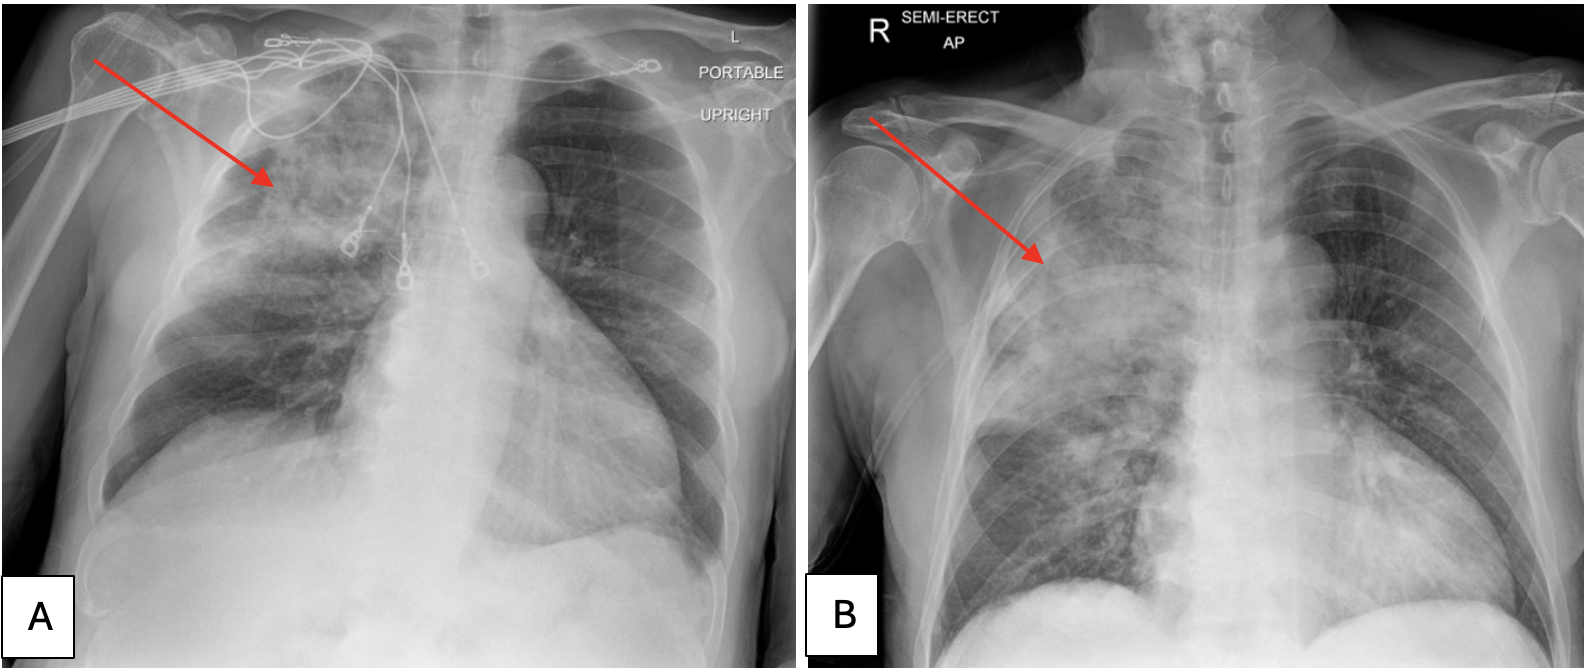

Case Presentation: We present a rare case of hydralazine-induced diffuse alveolar hemorrhage (DAH) in a 74-year-old male with a history of hypertension. The patient was admitted with symptoms including hemoptysis, dyspnea, and dark urine. Initial findings included a biopsy-confirmed leukocytoclastic vasculitis, elevated MPO antibodies, and evidence of DAH on bronchoscopy. Despite the absence of glomerulonephritis, the patient exhibited signs of pulmonary-renal syndrome, including worsening renal function and anemia. Notably, the patient developed melena (likely from aspiration of pulmonary hemorrhage per the gastroenterology team) and a down-trending hemoglobin to 6.8 g/dL (ref: 13.3-17.5 g/dL) which improved with a transfusion of 2 packed red blood cells. A bronchoscopy was also completed the same day which yielded heavy RBCs without organisms and a bronchoalveolar lavage suggestive of DAH. The patient’s condition improved significantly after cessation of hydralazine and initiation of intravenous methylprednisolone. On discharge, he continued 60 milligrams of methylprednisolone for 4 weeks with a taper for 5 additional weeks (decreasing 10 milligrams every week).